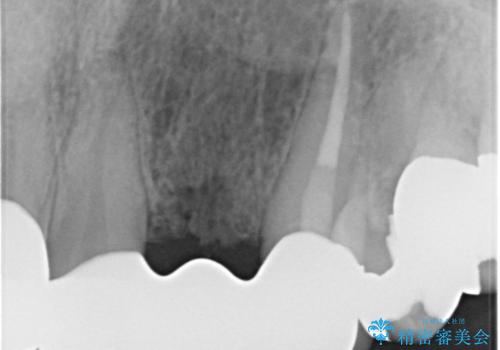

また、左上の犬歯の根の再治療も行いました。

- ジルコニアクラウンスタンダード・仮歯 13.2万円×6 左上3精密根管治療(リトリートメント)・ファイバーコア 12.1万円費用は治療当時の料金となります

最終的な被せ物は抜歯を行なってから半年経ってから形を整えて型取りを行います。